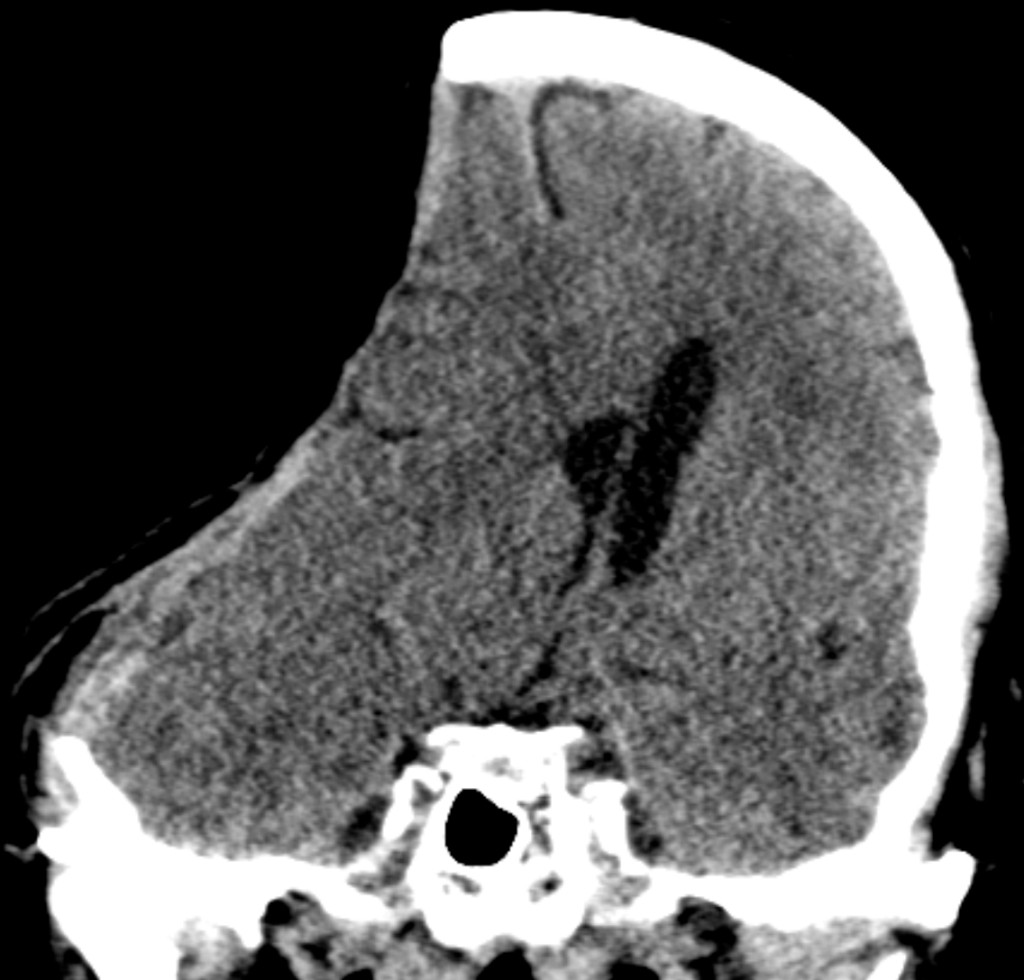

This image shows paradoxical brain herniation in a patient with known renal failure, hypertension and coronary artery disease who had undergone a hemicraniectomy a few months earlier. Paradoxical brain herniation is a rare, and potentially life-threatening, complication following removal of a large area of the skull. One of the roles of the skull is to protect the brain from the difference in intracranial pressure relative to atmospheric pressure. In larger craniectomies, the atmospheric pressure may exceed the intracranial pressure, causing displacement of underlying brain tissue and, at worst, herniation (1). The condition is most commonly seen with acute pressure changes following lumbar puncture or drainage of cerebrospinal fluid (with a shunt or ventricular drain) in patients who have undergone a craniectomy, and may be further exacerbated by dehydration or head-of-bed elevation. Acute treatment consists of lowering the head of the bed and making mechanical improvements to cerebrospinal fluid drainage if appropriate (adjusting the resistance of ventricular or lumbar drains), as well as replacing the bone flap if possible. Intensive treatment with overpressure ventilation (2) and fluid therapy or treatment of heart failure can alter the intracranial pressure and in some cases contribute to the development of this condition.